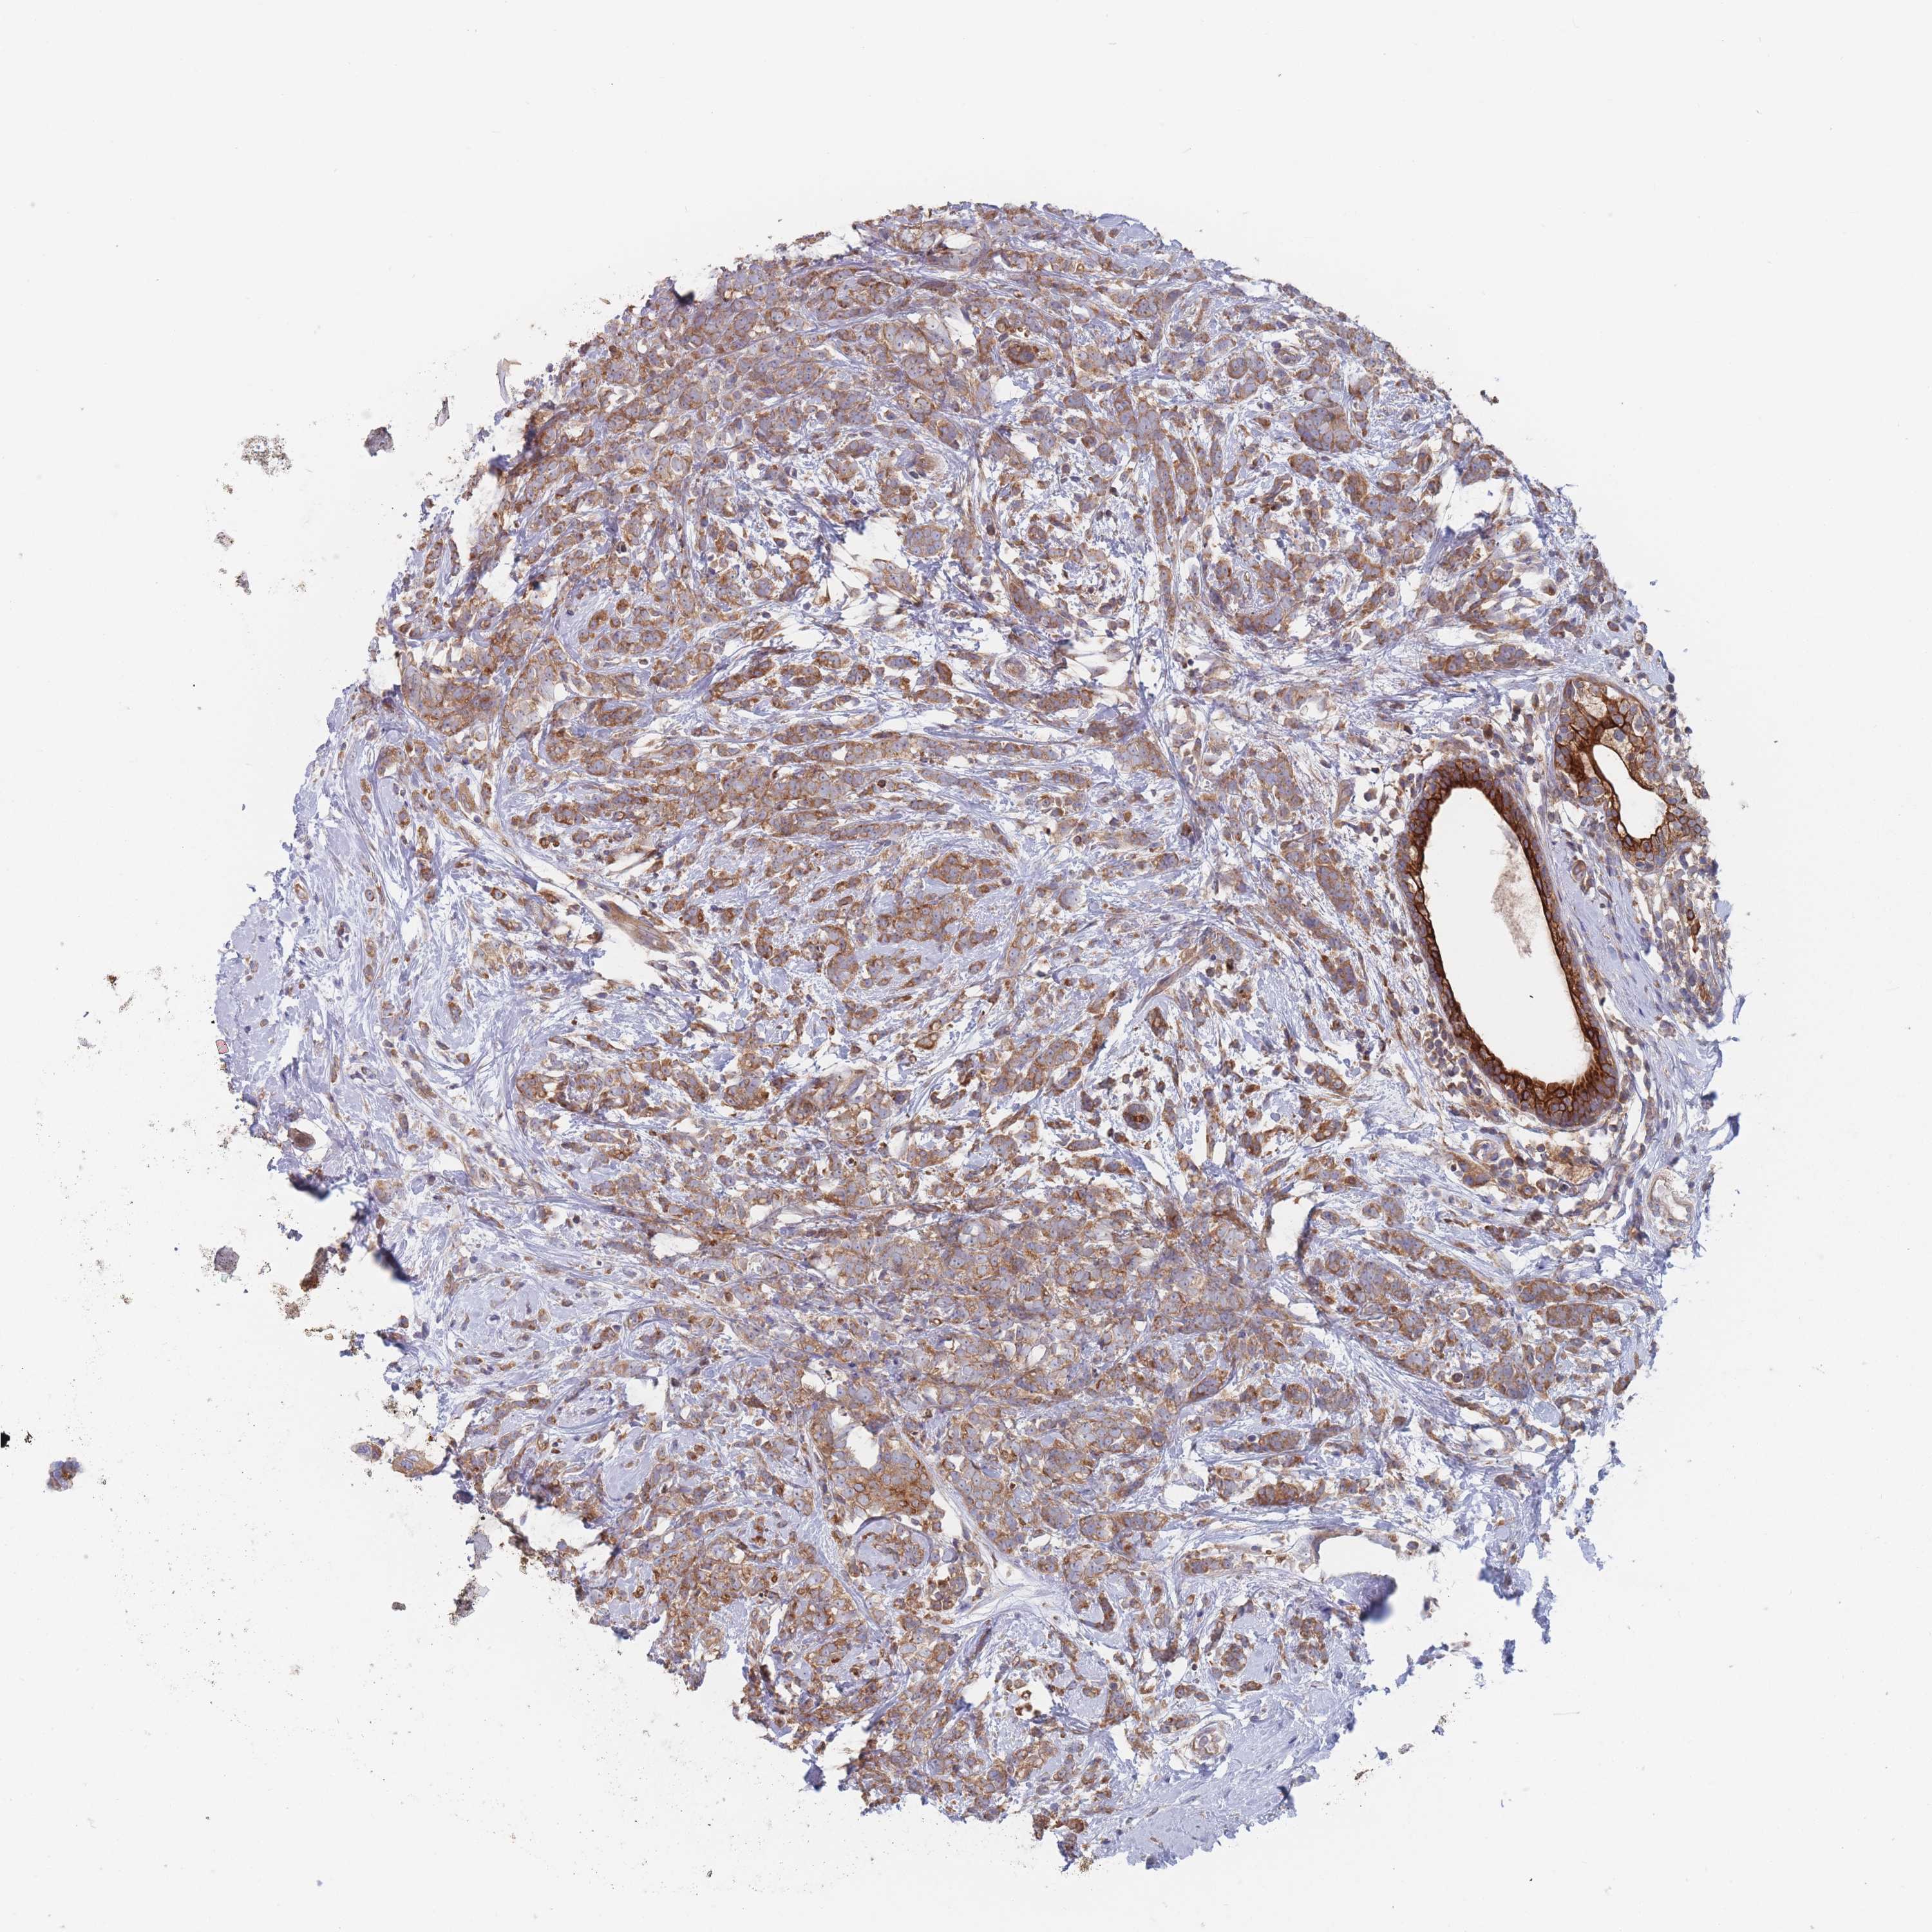

BRCA TCGA BRCA VALIDATION PROTEIN EXPRESSION

ANTIBODIES

AND

VALIDATION